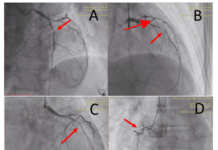

ĐẶT STENT ĐỘNG MẠCH CẢNH HAY CẮT BỎ NỘI MẠC ĐỘNG MẠCH CẢNH CHO HẸP ĐỘNG MẠCH CẢNH CÓ TRIỆU CHỨNG?

TRƯỜNG HỢP LÂM SÀNG